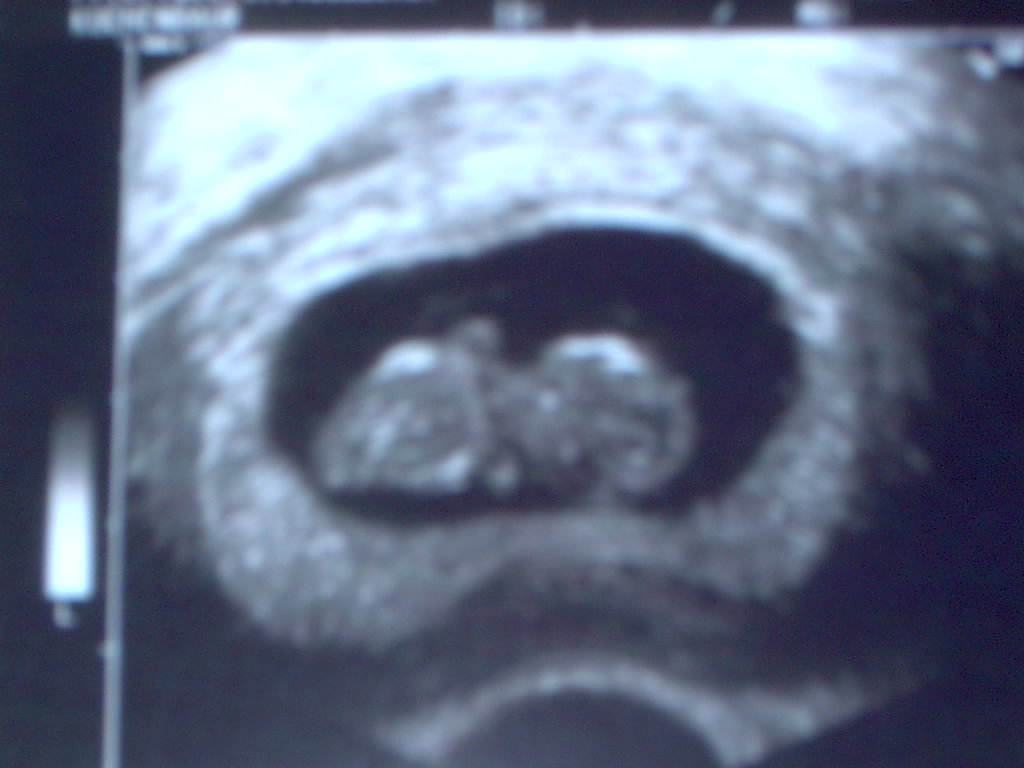

erst mal in mir gemütlich gemacht. Es sieht nämlich so aus, als ob sie ein paar Tage auf den ES warten mußten, da das Baby erst einige Tage nach dem

entstanden ist.

Zwergerl im Bauch